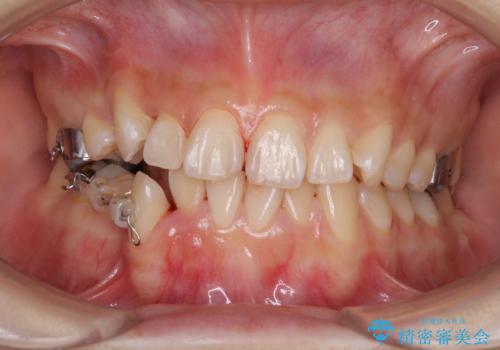

上下ともに八重歯の後ろの歯を1歯ずつ抜歯し、補助装置(リンガルアーチ)を用いて八重歯の位置を改善し、その後インビザラインにより矯正治療を行うこととしました。

途中海外留学をされたため、治療期間は長くなりましたが、事前に補助装置やワイヤー装置を併用したことで、きれいな歯列に仕上げることができました。